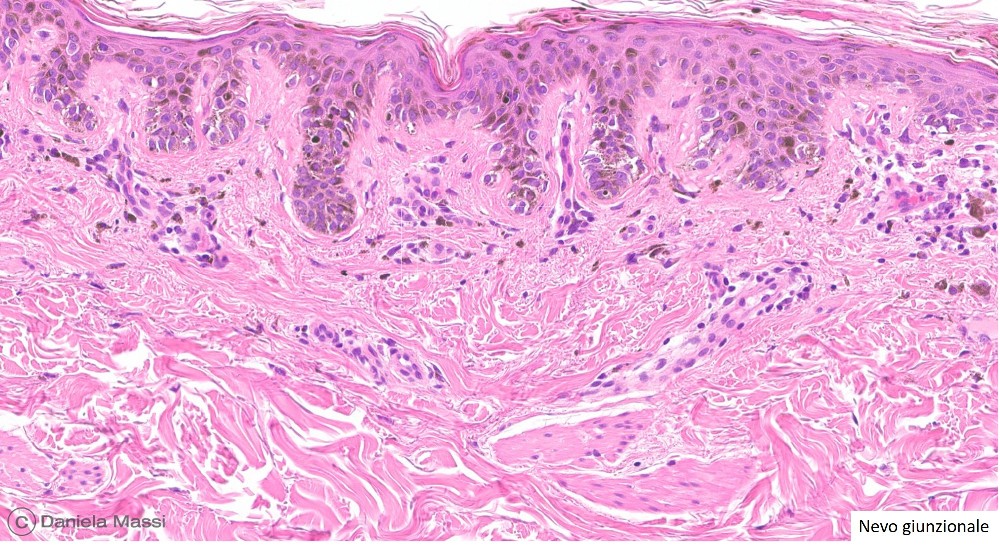

I nevi più comuni sono classificati istologicamente a seconda della loro prevalente localizzazione in relazione alla cute in: